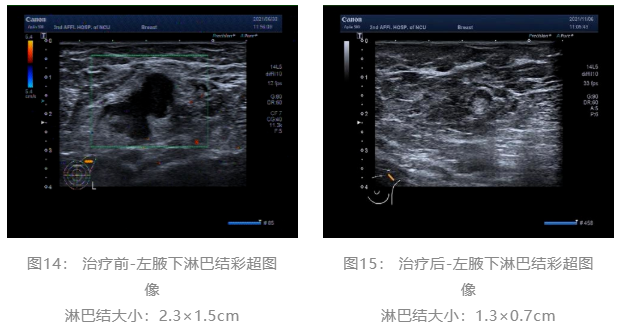

▌治疗前后影像学对比:

乳腺彩超:

术前评估:新辅助治疗期间患者无明显不适,一般状况可。新辅助治疗后左乳房肿瘤及腋下肿大淋巴结退缩明显,疗效评估PR,未发生不良事件,择期可行左乳癌改良根治术。